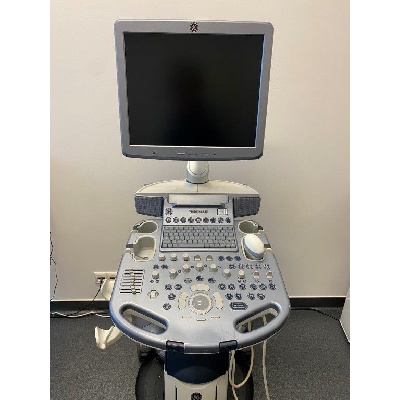

Használt Toshiba Xario SSA-660A kardiológiai ultrahang készülék

| Gyártó: | Egyéb |

|---|---|

| Pontos típus: | Toshiba SSA-660A, UILM-660A, UICW-660A |

| Gyártás éve: | 2012 |

| Műszaki állapot: | Újszerű |

Használt Toshiba Xario SSA-660A

| Gyártó: | Egyéb |

|---|---|

| Pontos típus: | Toshiba Xario SSA660A |

| Gyártás éve: | 2011 |

| Műszaki állapot: | Újszerű |